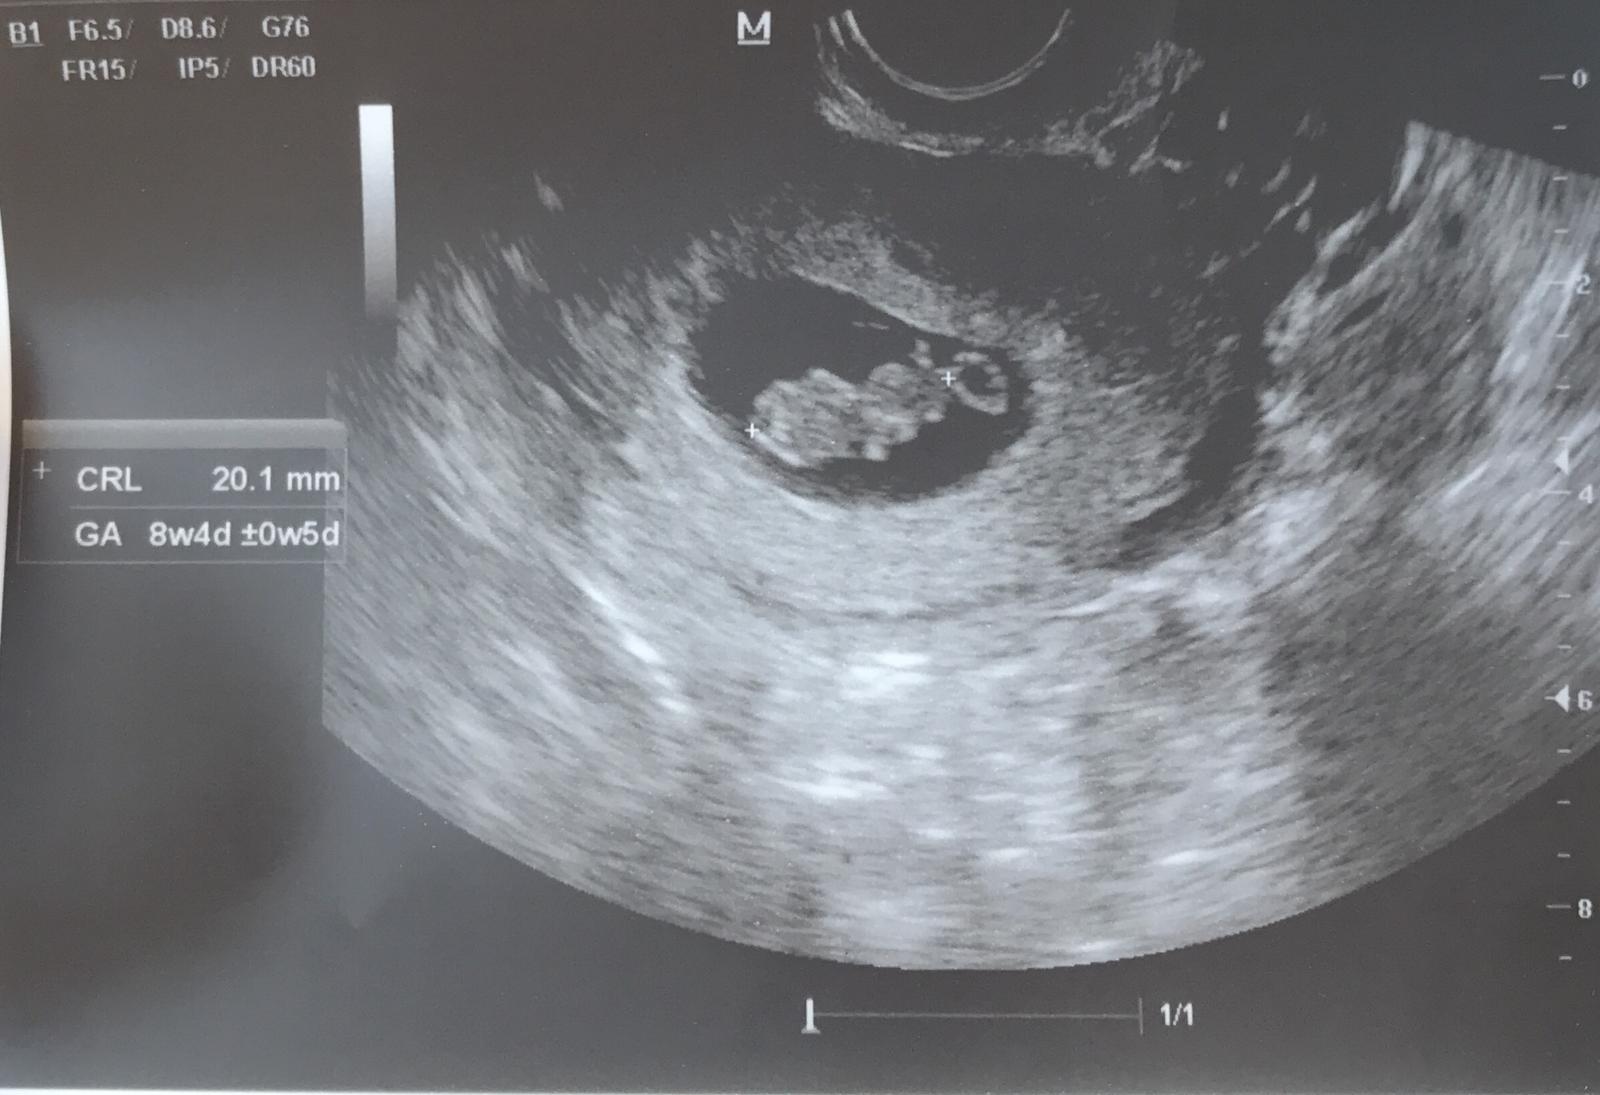

Je to pěkný se podívat na ten ultrazvuk z 7+1 /odpovídal přesně/ a pak z toho 9+4, kde tedy odpovídal 9+0